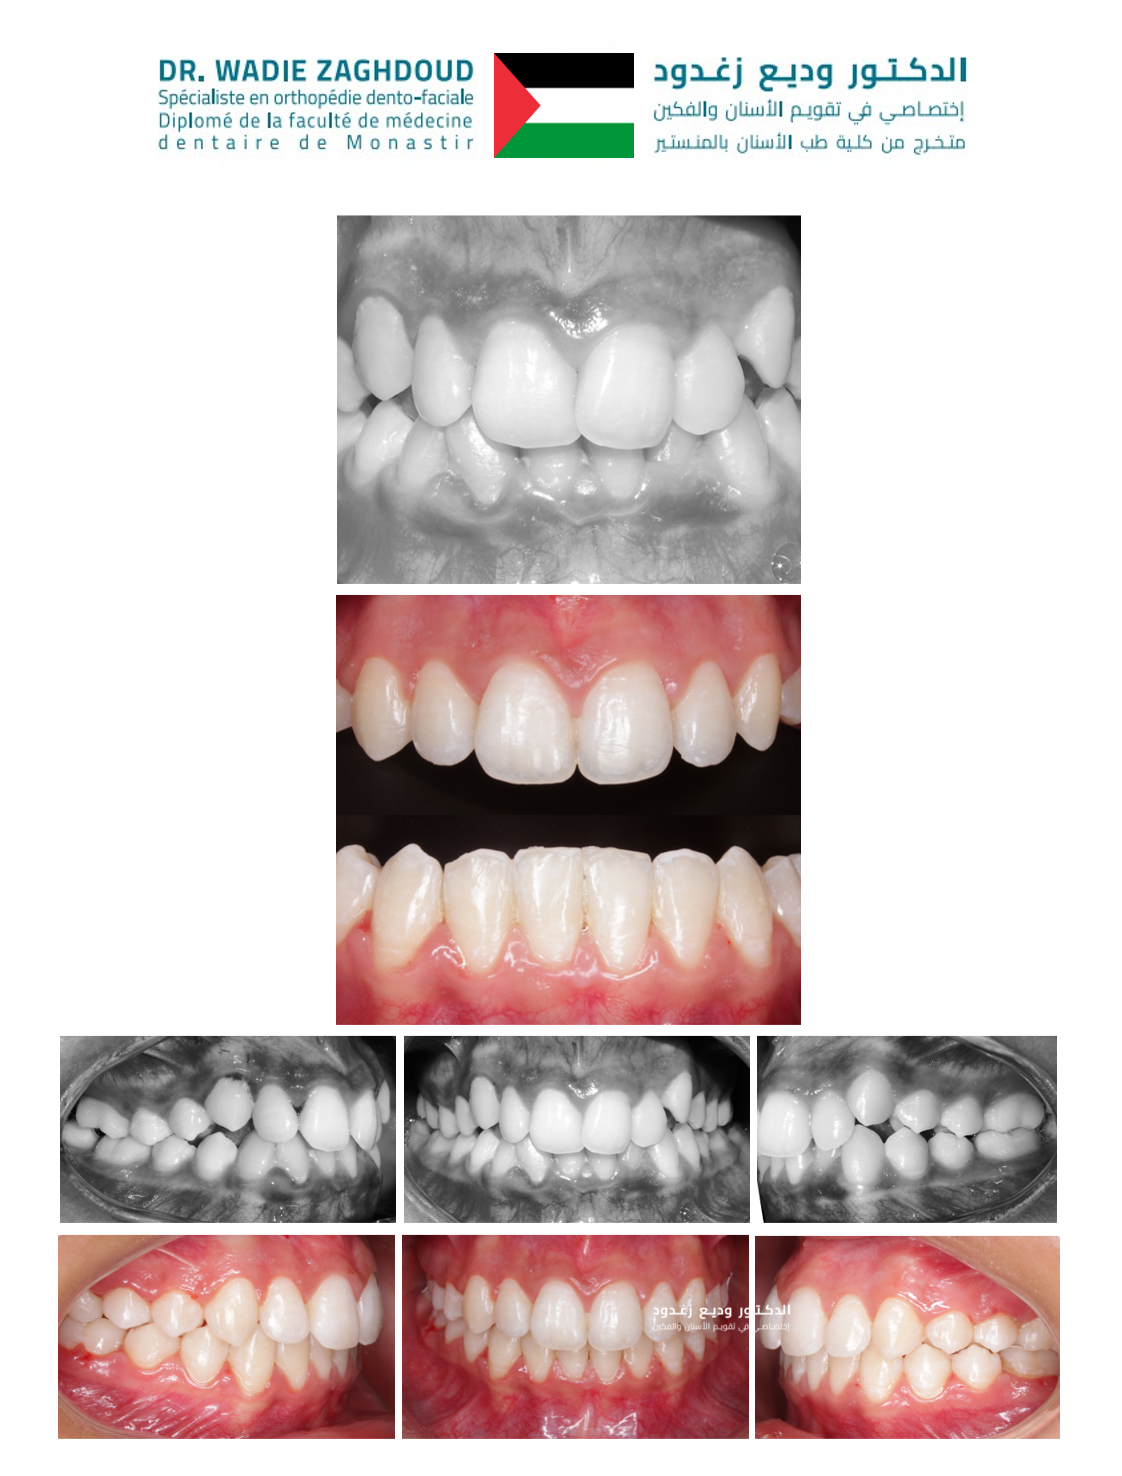

Orthodontie adulte-enfant Orthodontie invisible par aligneur Diplôme en médecine dentaire de la faculté de médecine dentaire de Monastir Diplôme en orthodontie de la faculté de médecine dentaire de Monastir Diplôme en orthodontie esthétique par aligneur Ancien membre de l’association internationale de recherche en médecine dentaire IADR Membre de la société européenne de l’orthodontie par aligneur Auteur de plusieurs articles scientifiques